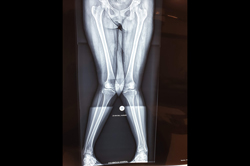

Deformity Correction - Genu Valgum